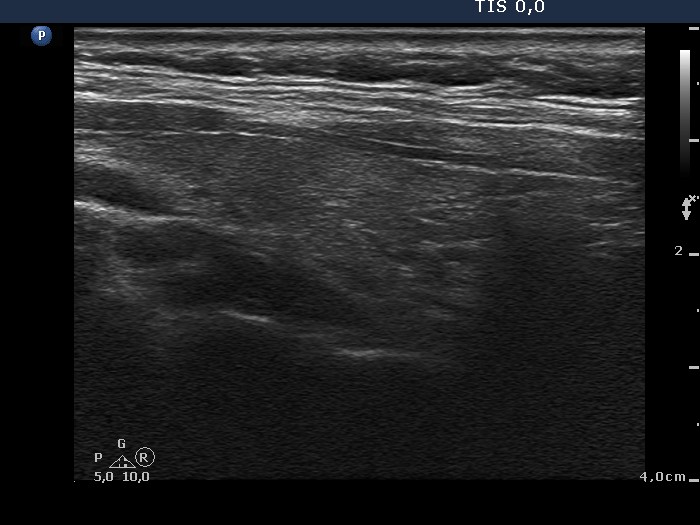

100 consecutive cases of papillary cancer - case 009 (ultrasonographic picture 2)

Right lobe, longitudinal scan.